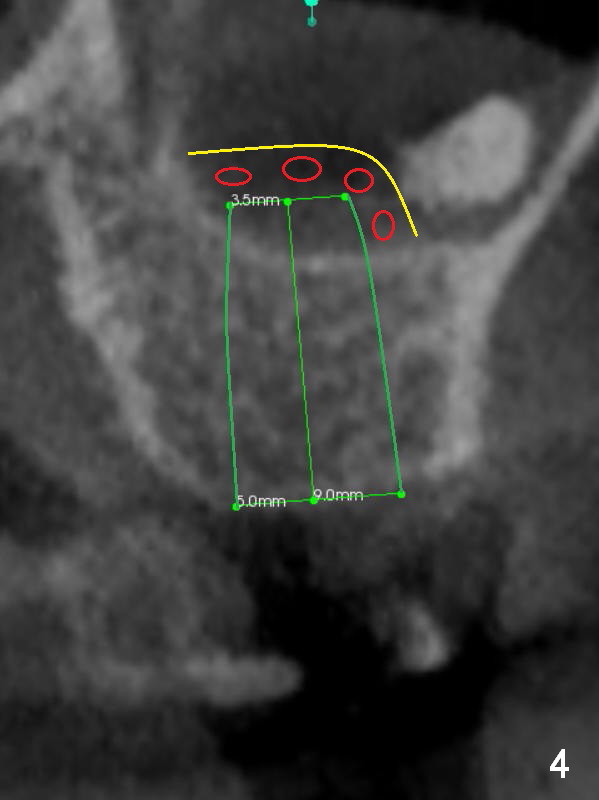

CT shows a residual root in the left maxillary sinus. In order not to re-infect the sinus, an implant at the site of #14 should not enter the sinus (Fig.2) or enters the sinus with bone graft (Fig.3,4 red circles) and more importantly PRF membrane (yellow).

Traditional segmental orthodontic treatment (open coil spring) is to be conducted to increase the mesiodistal width from 4.7 mm to 8 mm to place a 5 mm implant (Fig.2,3). Once the implant osteointegrates, it will be used an anchorage to further distalize the tooth #15.